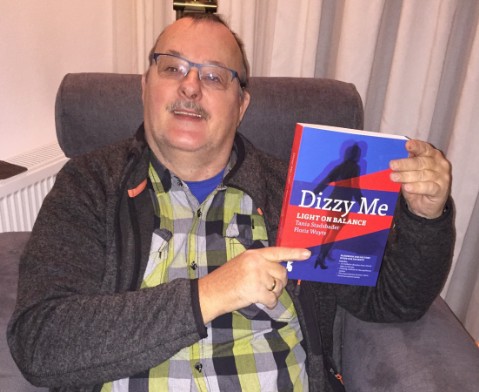

Jaaaaaa daar is ie dan. Het lang verwachte boek Dizzy Me.

Wat is het een spannende periode geweest vanaf de crowdfunding tot de uitgave van deze editie. Bloed, zweet en tranen, maar de auteurs van de Engelse editie van Dizzy Me, Tania en Floris, zijn erin geslaagd om een meesterwerk neer te zetten. Een handzaam boekwerk boordevol met actuele informatie. Een boek die thuishoort op de boekenplank van iedere KNO- of NPO-arts, waar ook ter wereld. Ze moeten er ook natuurlijk kennis van nemen, niet er alléén in ‘neuzen’. Medische studenten in opleiding moeten het als standaard werk bij zich hebben. Als dit allemaal gerealiseerd kan worden ziet de wereld van een patiënt, die een evenwichtsstoornis heeft, er een stuk evenwichtiger uit.

Ik kwam in 2015 de Nederlandse editie van dit boek op het spoor.

Na 5 jaar misdiagnoses door de KNO-artsen van het MCL te Leeuwarden werd door Professor dr. Floris Wuyts de juiste diagnose gesteld: Vestibulaire Paroxysmien (VP). Nu al ruim 400 dagen Dizzy Free.

Door het lezen van het boek Dizzy Me kwam ik er achter dat men bij het UZA te Antwerpen ver waren m.b.t. het onderzoeken naar evenwichtsstoornissen en het stellen van een juiste diagnose. Ik heb toen gevraagd om mij door te verwijzen naar het UZA, alwaar ik werd geholpen door professor dr. Floris Wuyts. Na onderzoek en gebruikmakende van de SO STONED methodiek stelde de professor bij mij de diagnose Vestibulaire Paroxysmien (VP). Door het innemen van de medicatie Carbamazepine zijn de evenwichtsstoornissen drastisch afgenomen. Het is de bedoeling dat ik in het voorjaar van 2017 de medicijnen ga afbouwen en weer een bezoek aan professor dr. Floris Wuyts ga brengen.

Het is van groot belang dat de patiënten en medici kennis gaat nemen van het boek Dizzy Me. Er lopen te veel patiënten rond in de wereld die een misdiagnose hebben en eerder zieker worden dan beter.

De Engelse versie verschijnt juni van dit jaar, evenals een Engelse E-book. Later dit jaar verschijnt er ook een Spaanse uitgave.

Floris Wuyts en Tania Stadsbader zijn de auteurs van het boek Dizzy Me. Een houvast voor de patiënt en een handboek voor de arts.

Tania kampte vijftien jaar met evenwichtsstoornissen. Pas na een operatie raakte ze van haar aandoening verlost. Het boek geeft een beeld van haar lange zoektocht naar de juiste diagnose en de impact en naweeën van jaren ziek zijn. Tania brengt haar verhaal heel direct en geeft lotgenoten een stem. Floris Wuyts maakt het boek helemaal af met zijn wetenschappelijke benadering en de meest recente bevindingen.

Deze baanbrekende mix van patiënt en prof maakt dit boek uniek in zijn soort.

Kijk ook op www.dizzyme.eu.